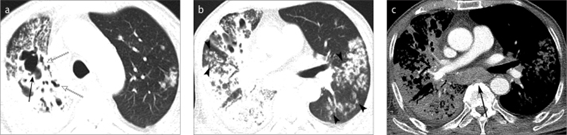

Hình ảnh CT cho thấy tổn thương ở cả hai bên và toàn bộ thùy phổi ở bệnh nhân lao phổi kèm đái tháo đường [13].

![]() |

Hình ảnh CT cho thấy tổn thương ở cả hai bên và toàn bộ thùy phổi ở bệnh nhân lao phổi có kèm đái tháo đường [13].